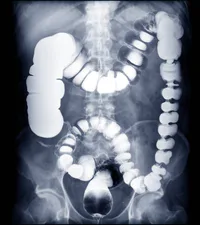

What's the degree of rotation for the oblique positions (LAO, RAO, LPO, RPO) of the BE-Large Intestine?

The (a) is the most proximal portion of the large intestine.

The (a) is the most distal portion of the Small Intestine.